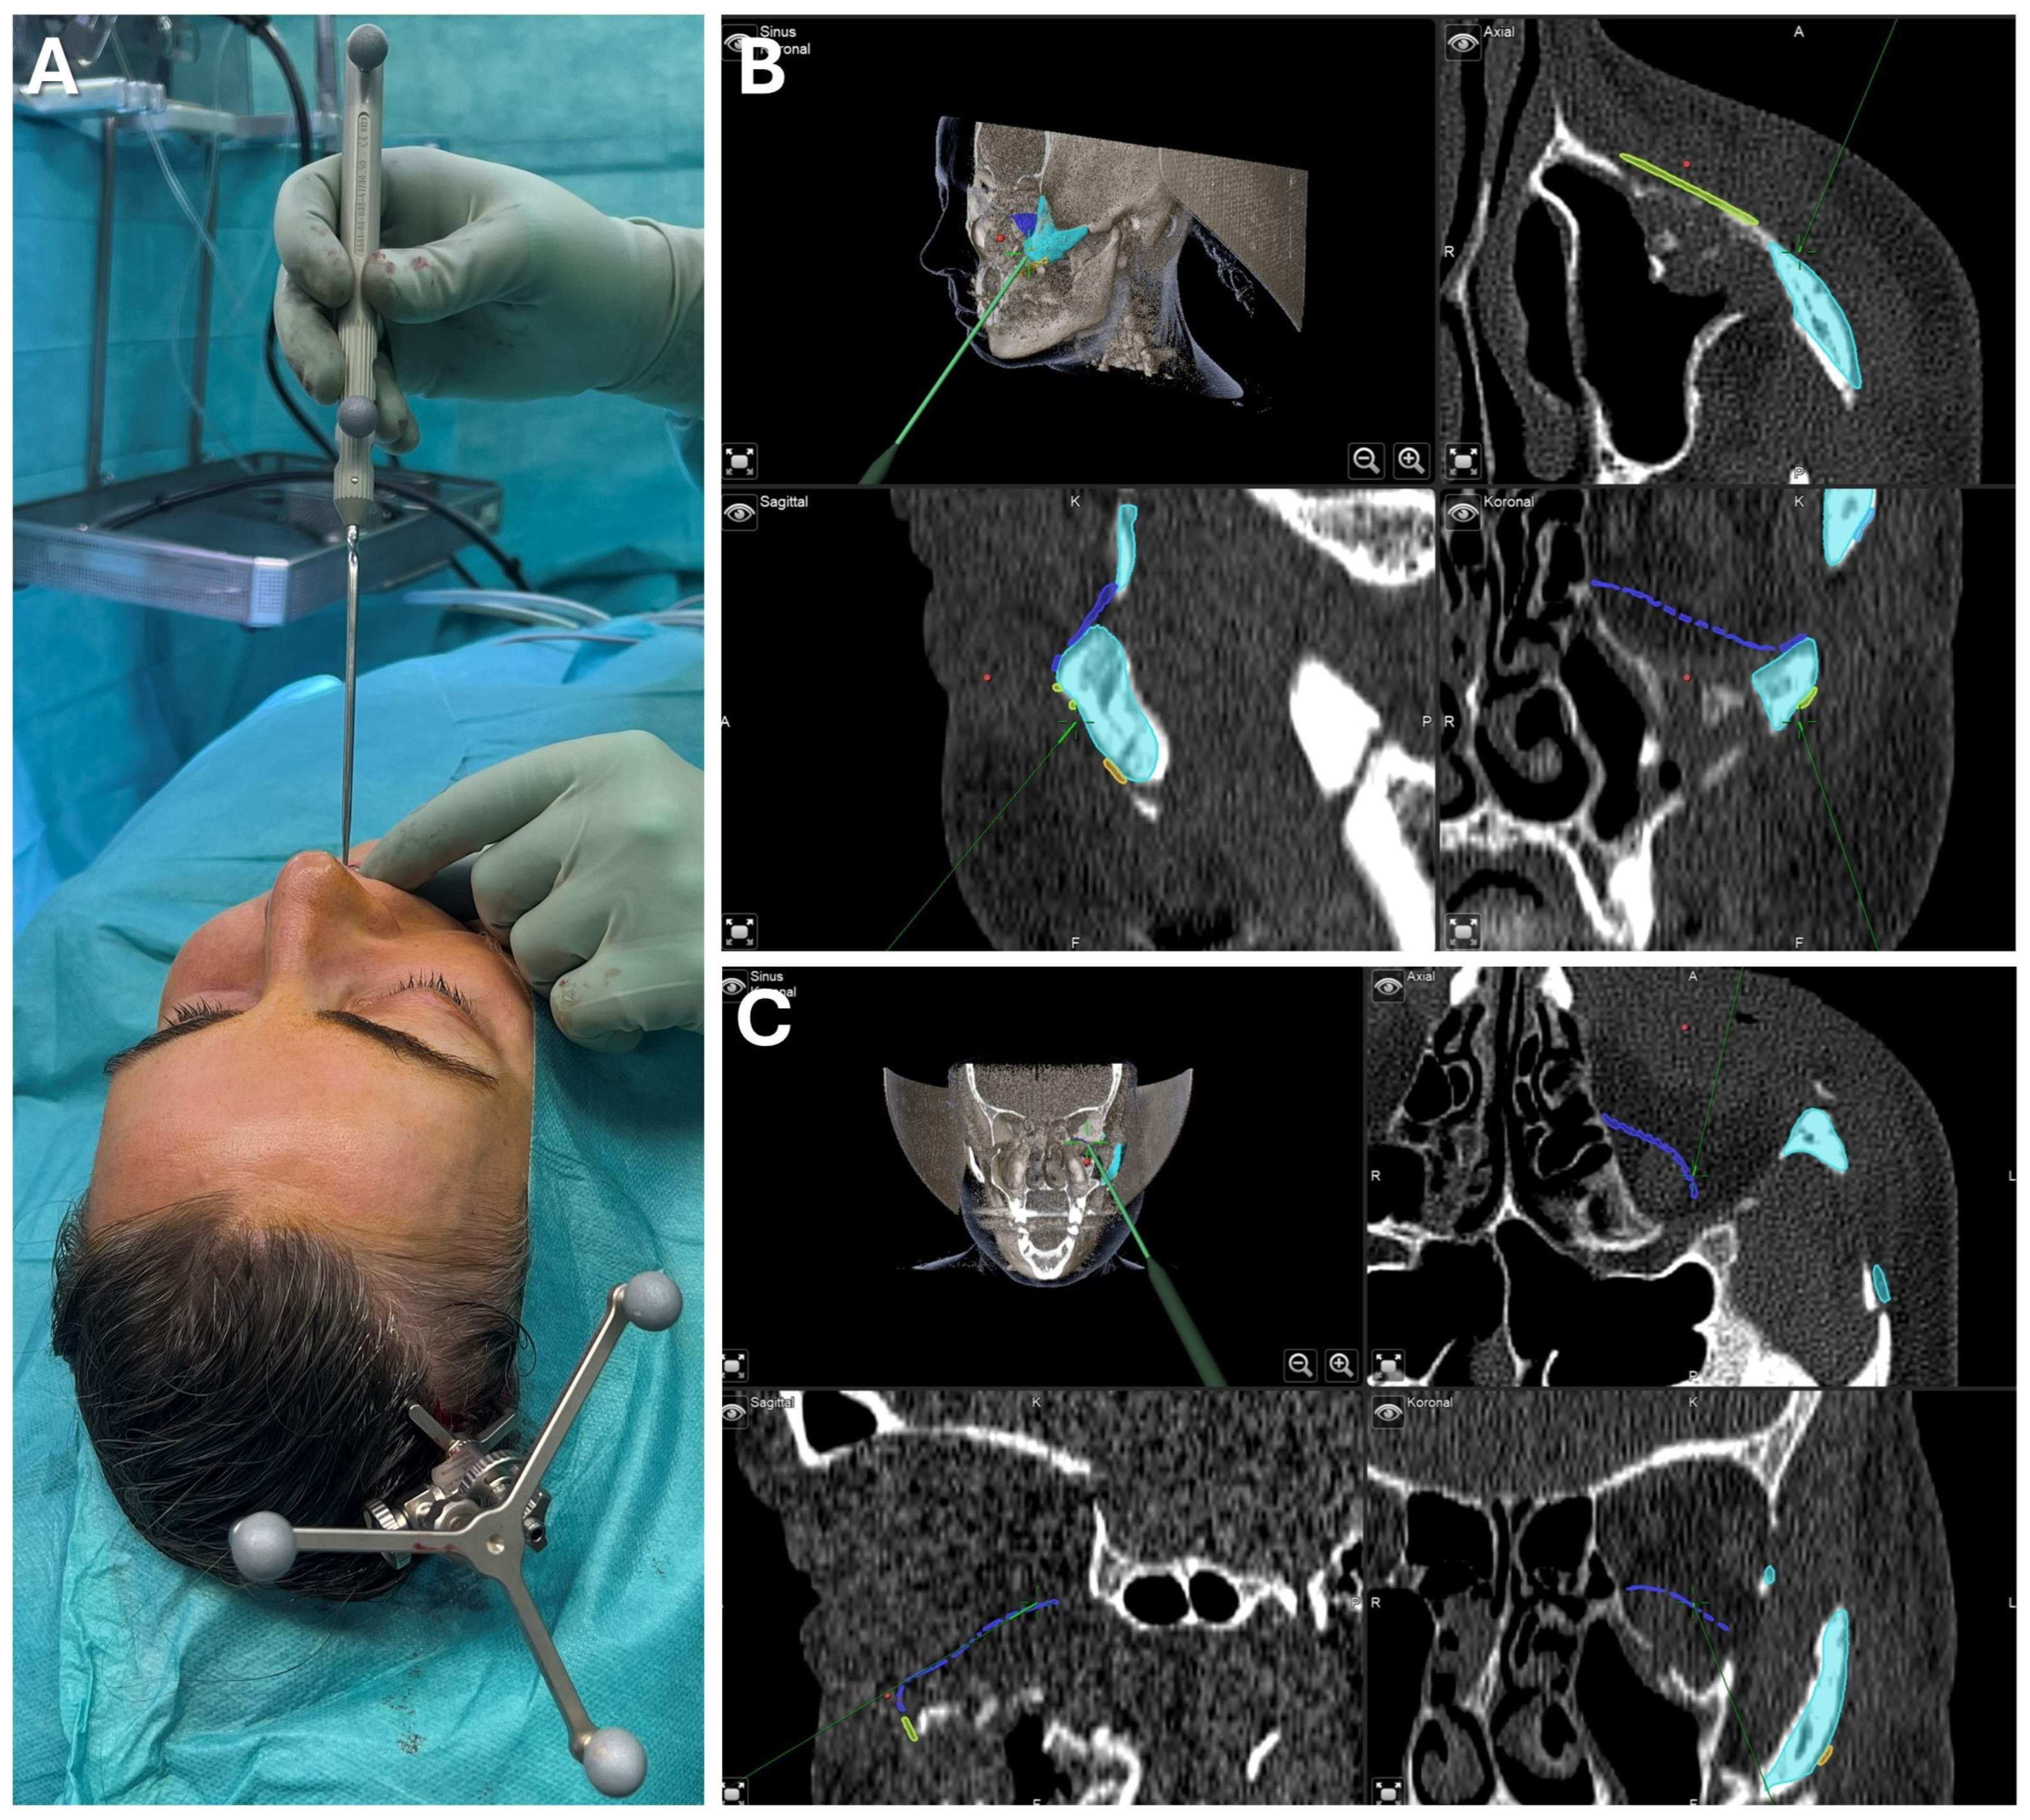

3.2.1. Case 1: Secondary Zygoma and Orbital Floor Repair Following Trauma

3.2.2. Case 2: Mandibular Recontouring in a Case of Benign Central Osteoma